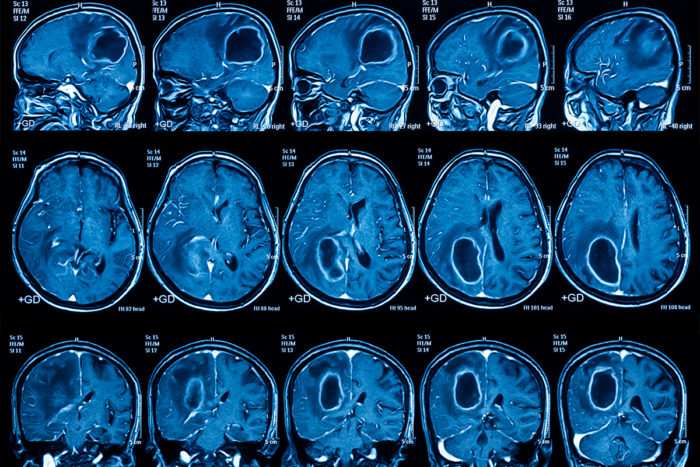

Most people with the deadly brain cancer glioblastoma die less than 18 months after diagnosis. But a multicenter clinical trial of a personalized vaccine that targets the aggressive cancer has indicated improved survival rates for such patients. The study appears May 29 in the Journal of Translational Medicine. The phase three clinical trial included 331 […]